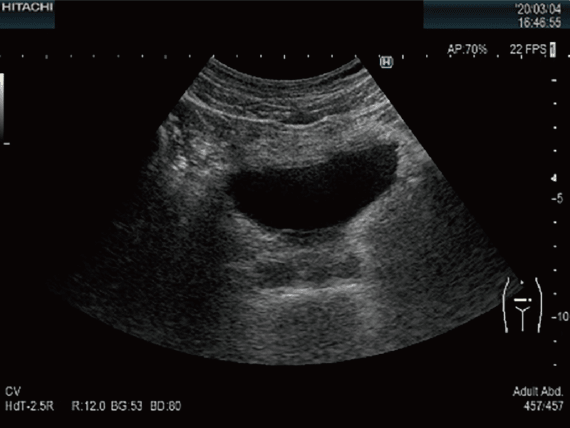

泌尿器超音波検査

腹部と背部より超音波を照射して,腎臓・副腎・膀胱・前立腺などの腹腔内臓器・骨盤内臓器を観察する検査です。各種臓器の腫瘍をはじめとして,結石,嚢胞などの発見や形態の評価に用いられます。